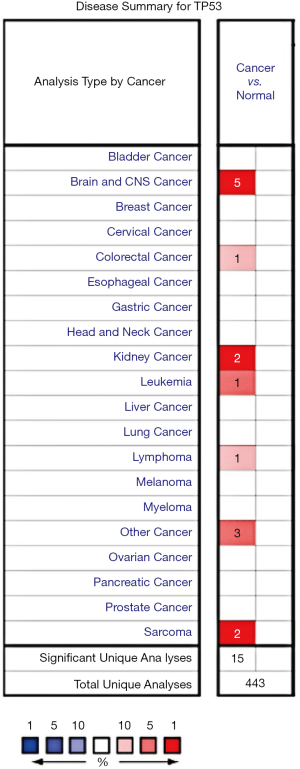

The Oncomine database was used to investigate the TP53 mRNA expression levels in various cancers. The results showed that TP53 is overexpressed in cancers of the brain and the central nervous system, as well as in colorectal cancer, kidney cancer, leukemia, lymphoma, and sarcoma (Figure 1).